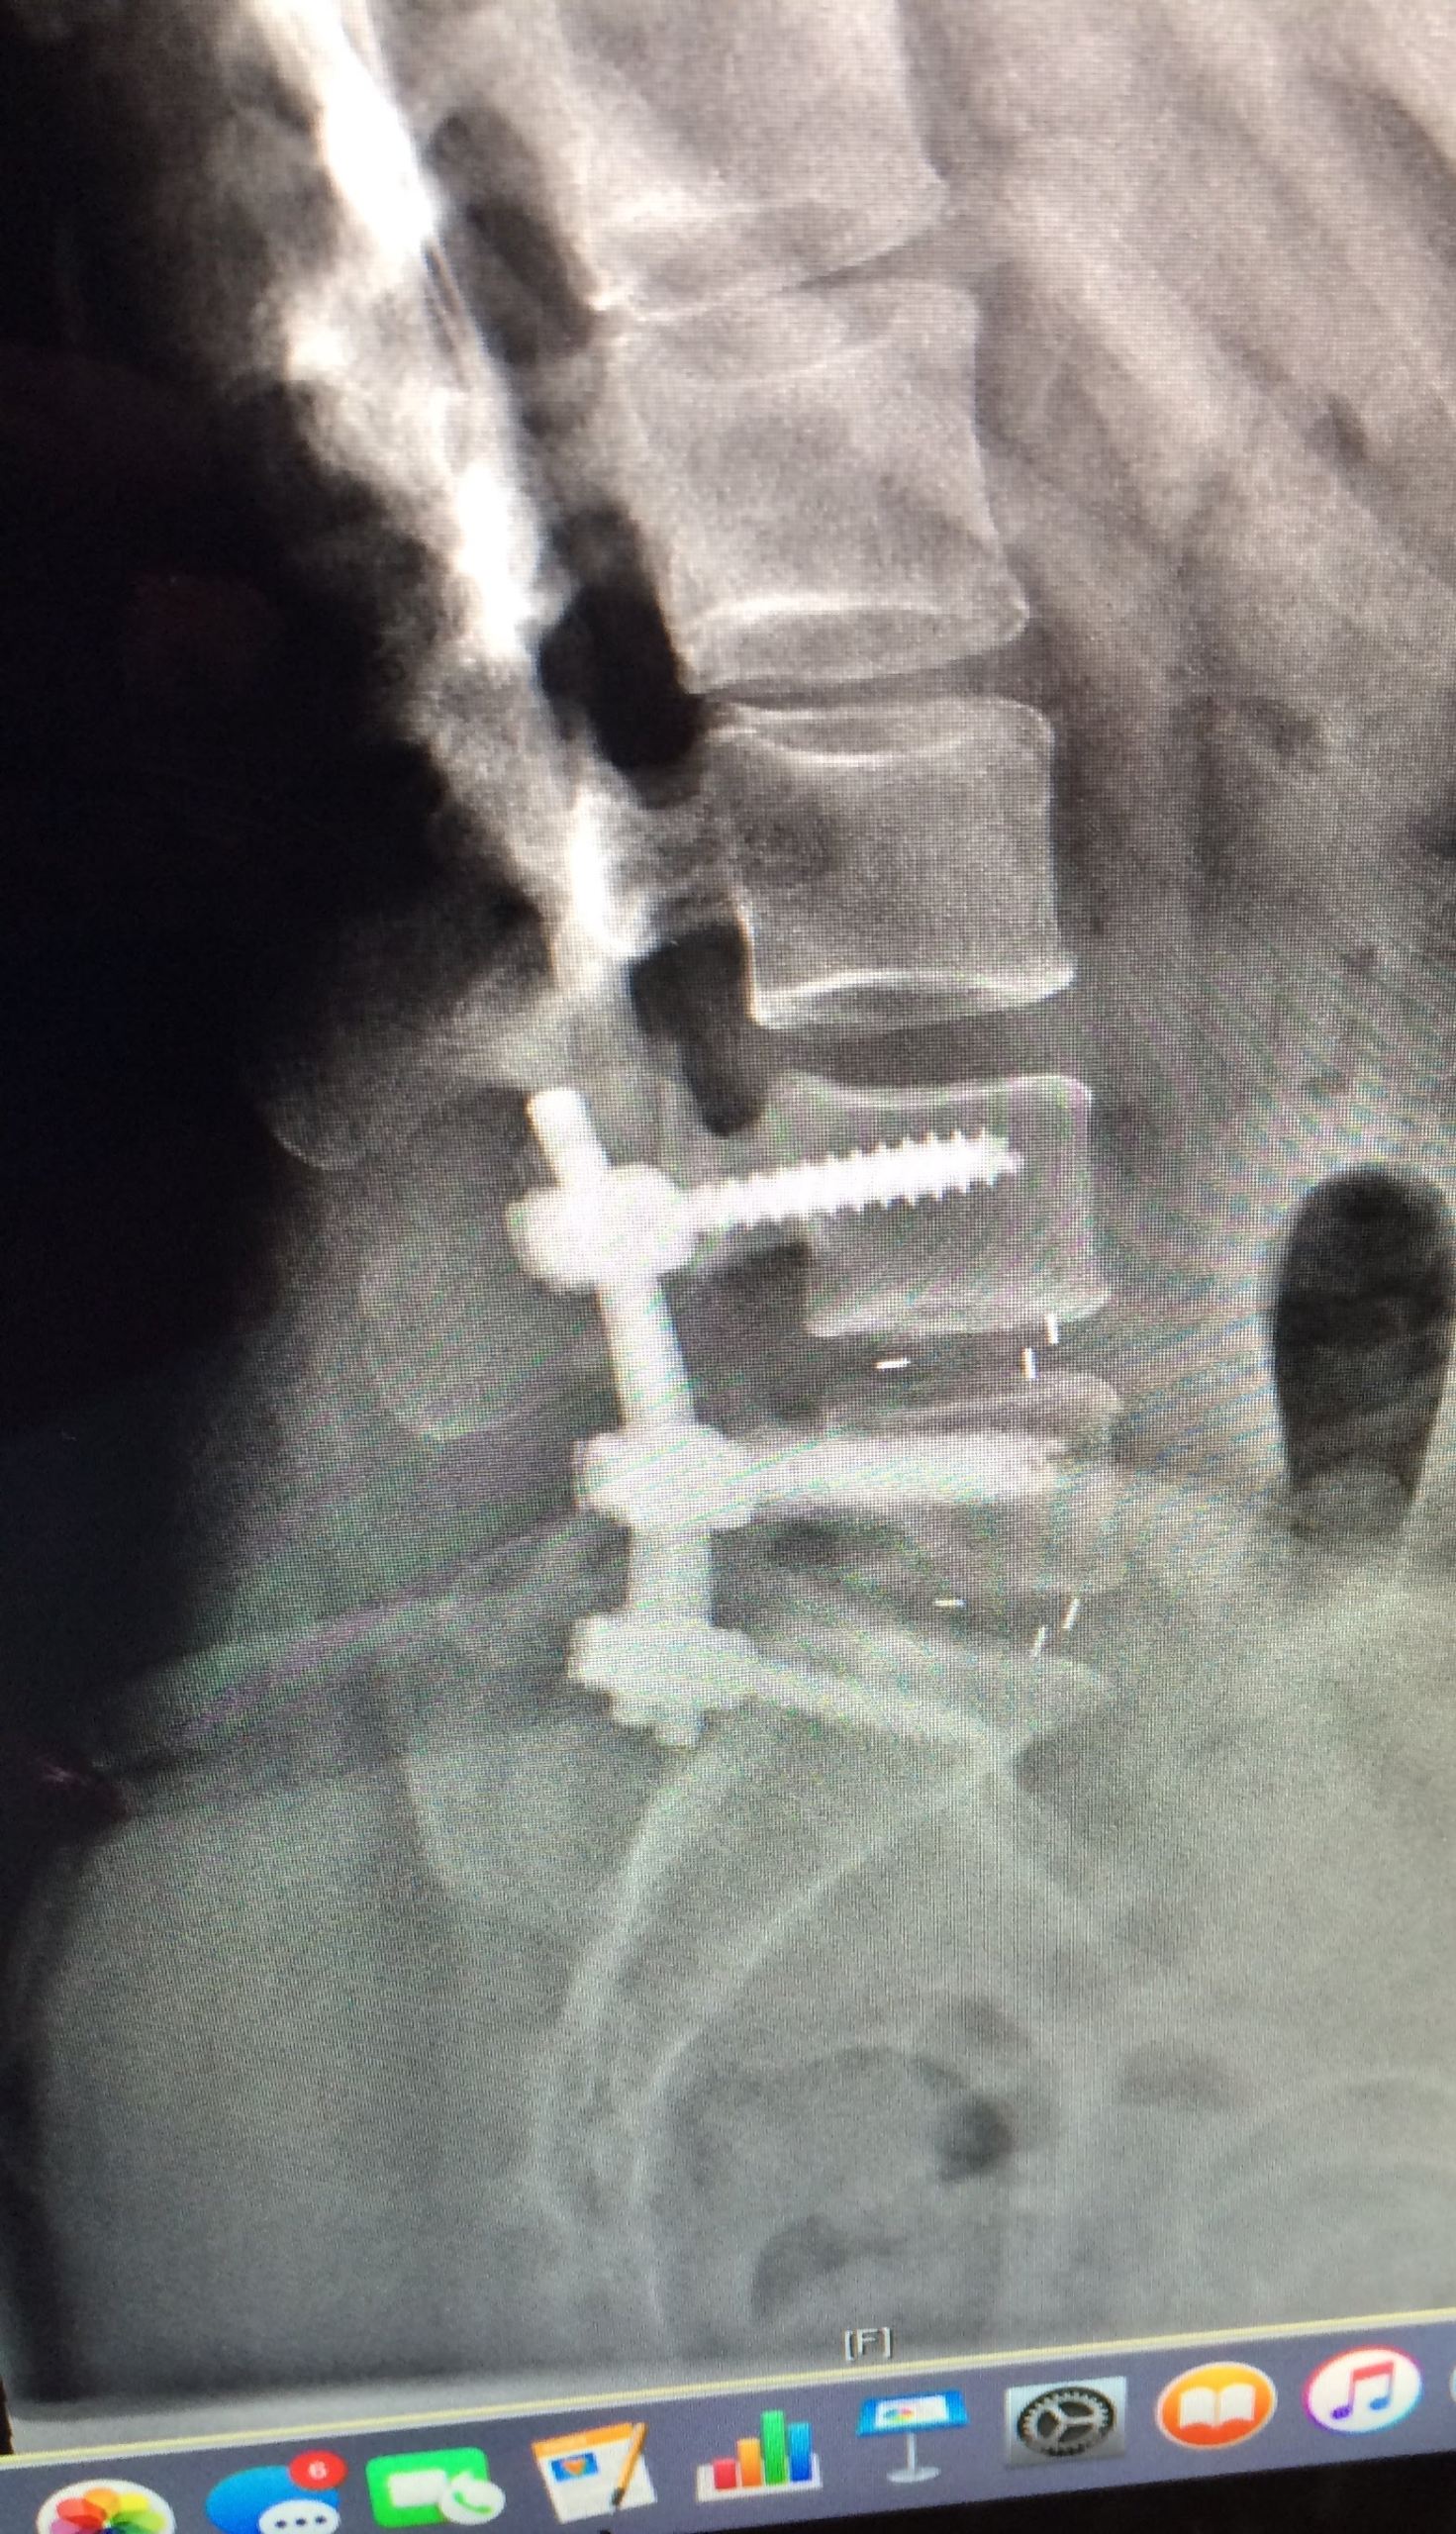

Mr Kelleher sat and listened, he then talked through my options and sat again answering all my questions. When we finally decided on lumbar fusion L4/L5/S1 I was anxious but again, Mr Kelleher talked me through everything. Throughout my stay in SSC I can honestly say every receptionist, nurse, house doctor, phlebotomist, radiographer, catering staff , manager that I interacted with gave me all the time I needed and explained everything and asked questions.